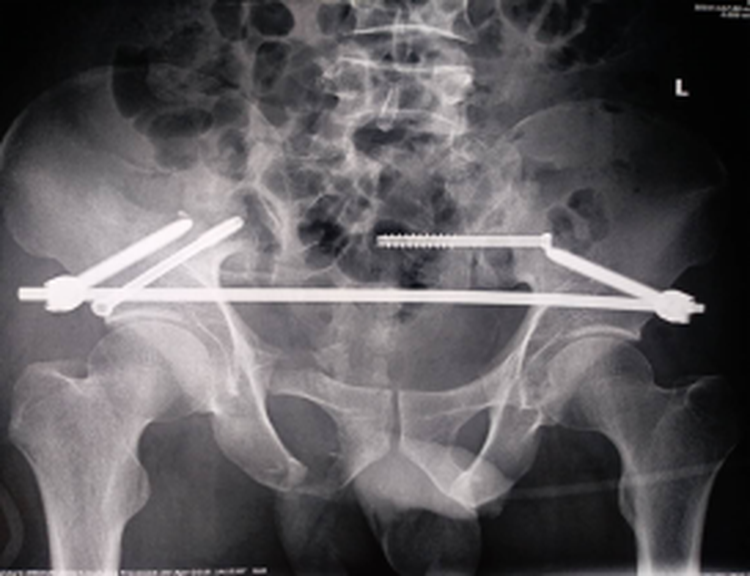

近日,我院骨创伤二科张鹏主任团队在北京301医院创伤骨科陈华教授的指导下,圆满完成了两例复杂骨盆骨折,两例手术都非常成功,术后病人恢复正常。

以往骨盆手术,传统手术方法需切开多个大型切口,肌肉组织剥离广泛、出血多,应用骨盆骨折闭合复位微创技术后,只是几个小切口,出血量减少至50ml以内,且基本不造成肌肉软组织损伤,手术时间缩短,使患者不必再忍受传统手术大切口的痛苦,而且能够确保骨折部位的精准复位和牢固固定。术后两名患者病情日渐好转。

张鹏主任表示,骨盆骨折微创治疗是目前骨盆骨折的最佳治疗法,为患者的生命安全和功能康复提供了保障,提升了我院创伤骨科的综合治疗水平。